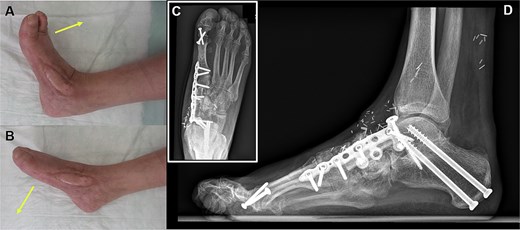

Six months after surgery, the final result shows a stable coverage with an adequate range of active motion regarding (A) dorsal extension and (B) plantar flexion. (C, D) The bone graft is fully integrated.